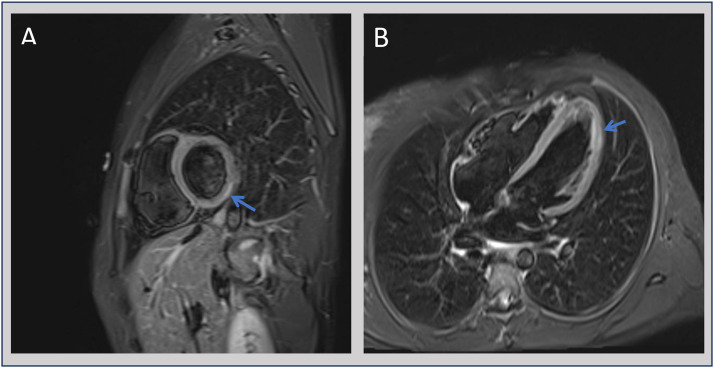

急性心肌炎是心肌的一种炎症,最常见的是由病毒感染引起的。细菌性心肌炎,特别是由于非伤寒沙门氏菌(NTS),是非常罕见的免疫正常的个体。我们报告一例罕见的沙门氏菌胃肠炎继发急性心肌炎病例,患者为23岁女性,其特征是心脏生物标志物升高,肠道沙门氏菌粪便培养阳性,心电图改变,心脏磁共振成像证实。治疗是保守的抗炎单药治疗,没有抗生素治疗,导致临床完全恢复,症状缓解,心脏生物标志物正常化。这个病例强调了一个罕见的nts相关心肌炎的表现,并建议保守管理可能足以在选定的病例。它强调了在急性心肌炎的鉴别诊断中考虑包括NTS在内的细菌性病原体的重要性,即使在免疫功能正常的患者中也是如此,并强调了多模式成像和个体化治疗策略在细菌性心肌炎中取得良好结果的效用。

Acute myocarditis is an inflammatory condition of the heart muscle, most commonly caused by viral infections. Bacterial myocarditis, particularly due to non-typhoidal Salmonella (NTS), is exceptionally uncommon in immunocompetent individuals. We report a rare case of acute myocarditis secondary to Salmonella gastroenteritis in a woman in her early 20s, characterised by elevated cardiac biomarkers, positive stool cultures for Salmonella enterica, electrocardiographic changes and confirmatory cardiac magnetic resonance imaging. Management was conservative with anti-inflammatory monotherapy without antibiotic treatment, resulting in full clinical recovery with resolution of symptoms and normalisation of cardiac biomarkers. This case highlights a rare presentation of NTS-associated myocarditis and suggests that conservative management may be sufficient in selected cases. It underscores the importance of considering bacterial pathogens, including NTS, in the differential diagnosis of acute myocarditis, even in immunocompetent patients, and highlights the utility of multimodal imaging and individualised management strategies in achieving favourable outcomes in bacterial myocarditis.